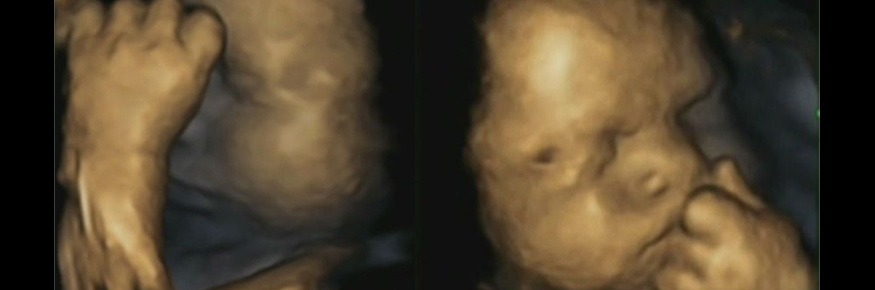

Researchers are using 4D scanning technology to discover how foetuses respond to shapes of light and sound.

Lancaster University are working with Blackpool Teaching Hospitals NHS Foundation Trust to find out the responses of foetuses at approximately 32 to 34 weeks of development.

Researchers want to see if these behaviours develop before birth by looking at the facial reactions to light and sound in babies just a few weeks before birth. This will help us to understand more about how babies understand other people during early development.

“We know that after birth all these things can be done by a baby. Only recently have we discovered that light is seen by the baby all the time before birth. Now that 4D scanning is possible, it is a perfect time for us to finally discover what is going on."